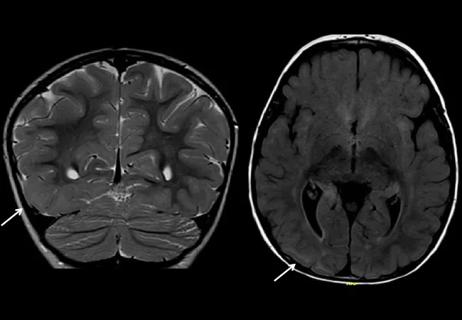

Case Study: A Toddler With Seizures, Hypsarrhythmia and an Evolving MRI

Would you recommend surgery in this challenging case?